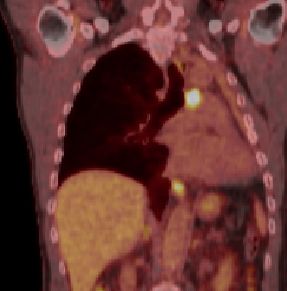

| PET-CT | 60jähriger Mann 18 Monate nach Pneumektomie links wegen Plattenepithelkarzinom des linken Lungenoberlappens pT2a pNo Mo![]() ![]() |